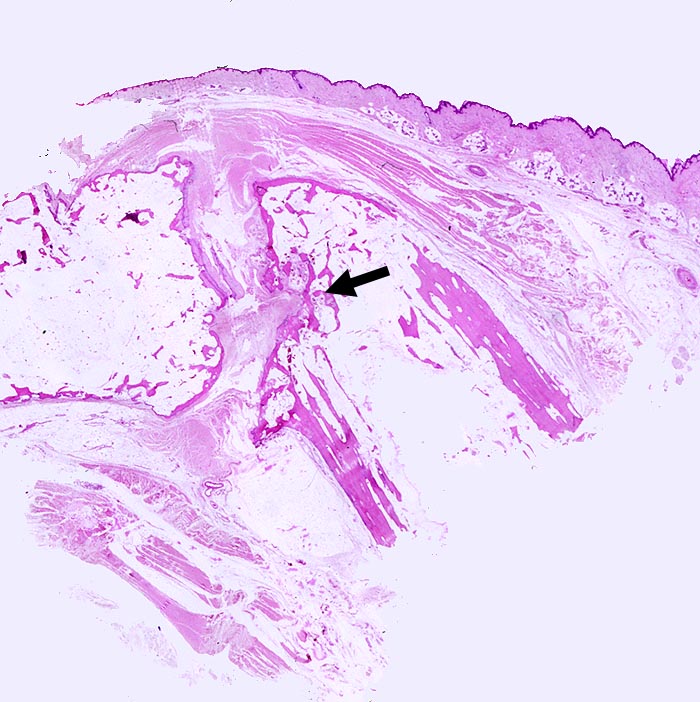

Rheumatoide Arthritis Interphalangealgelenk

Entzündung / Reparatur

Gelenk, Hand

Weichteile

Interphalangealgelenk mit sehr unregelmässiger Gelenkfläche und praktisch fehlendem Knorpel. Im Gelenkspalt bindegewebiger Pannus.

Dieser zerstört ► an einer Stelle die Gelenkfläche und dringt in die Spongiosa ein.

Seropositive rheumatoide Arthritis.

Histologie